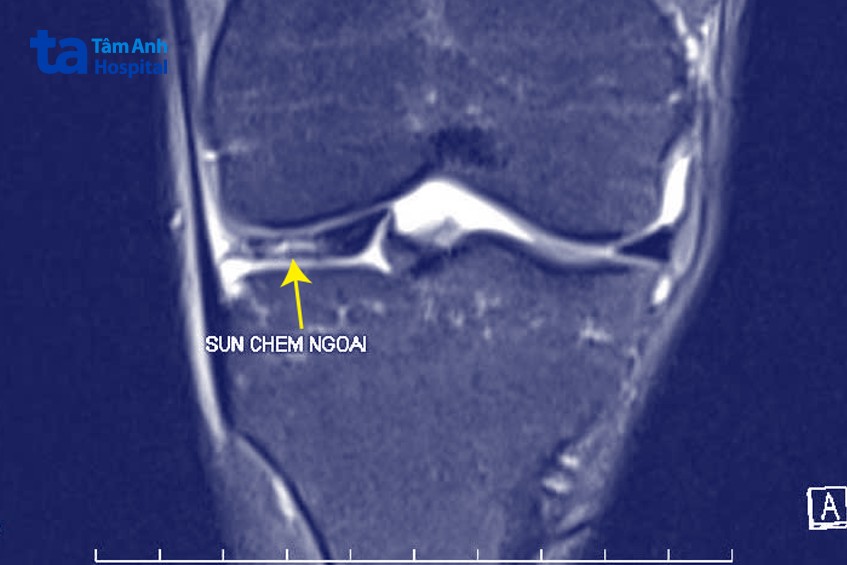

Tại Bệnh viện Đa khoa Tâm Anh Hà Nội, TS.BS Chế Đình Nghĩa (Phó khoa Chấn thương Chỉnh hình) thăm khám, chỉ định chụp MRI gấp. Kết quả cho thấy chị Vân có tổn thương sụn chêm dạng rách quai xô phức tạp – dạng rách dài khiến mảnh sụn cuộn vào giữa khớp. Phần sụn bị rách di lệch, chui vào khoang khớp gây hiện tượng “kẹt gối” (không thể gập duỗi).